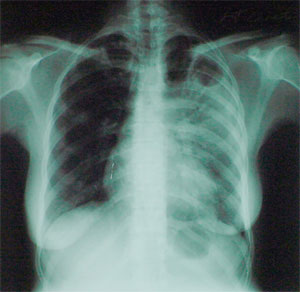

Туберкулез является инфекционной бактериальной болезнью, вызываемой микобактерией туберкулеза, которая наиболее часто поражает легкие. Он передается от человека к человеку капельным путем от людей, больных активной респираторной формой болезни.